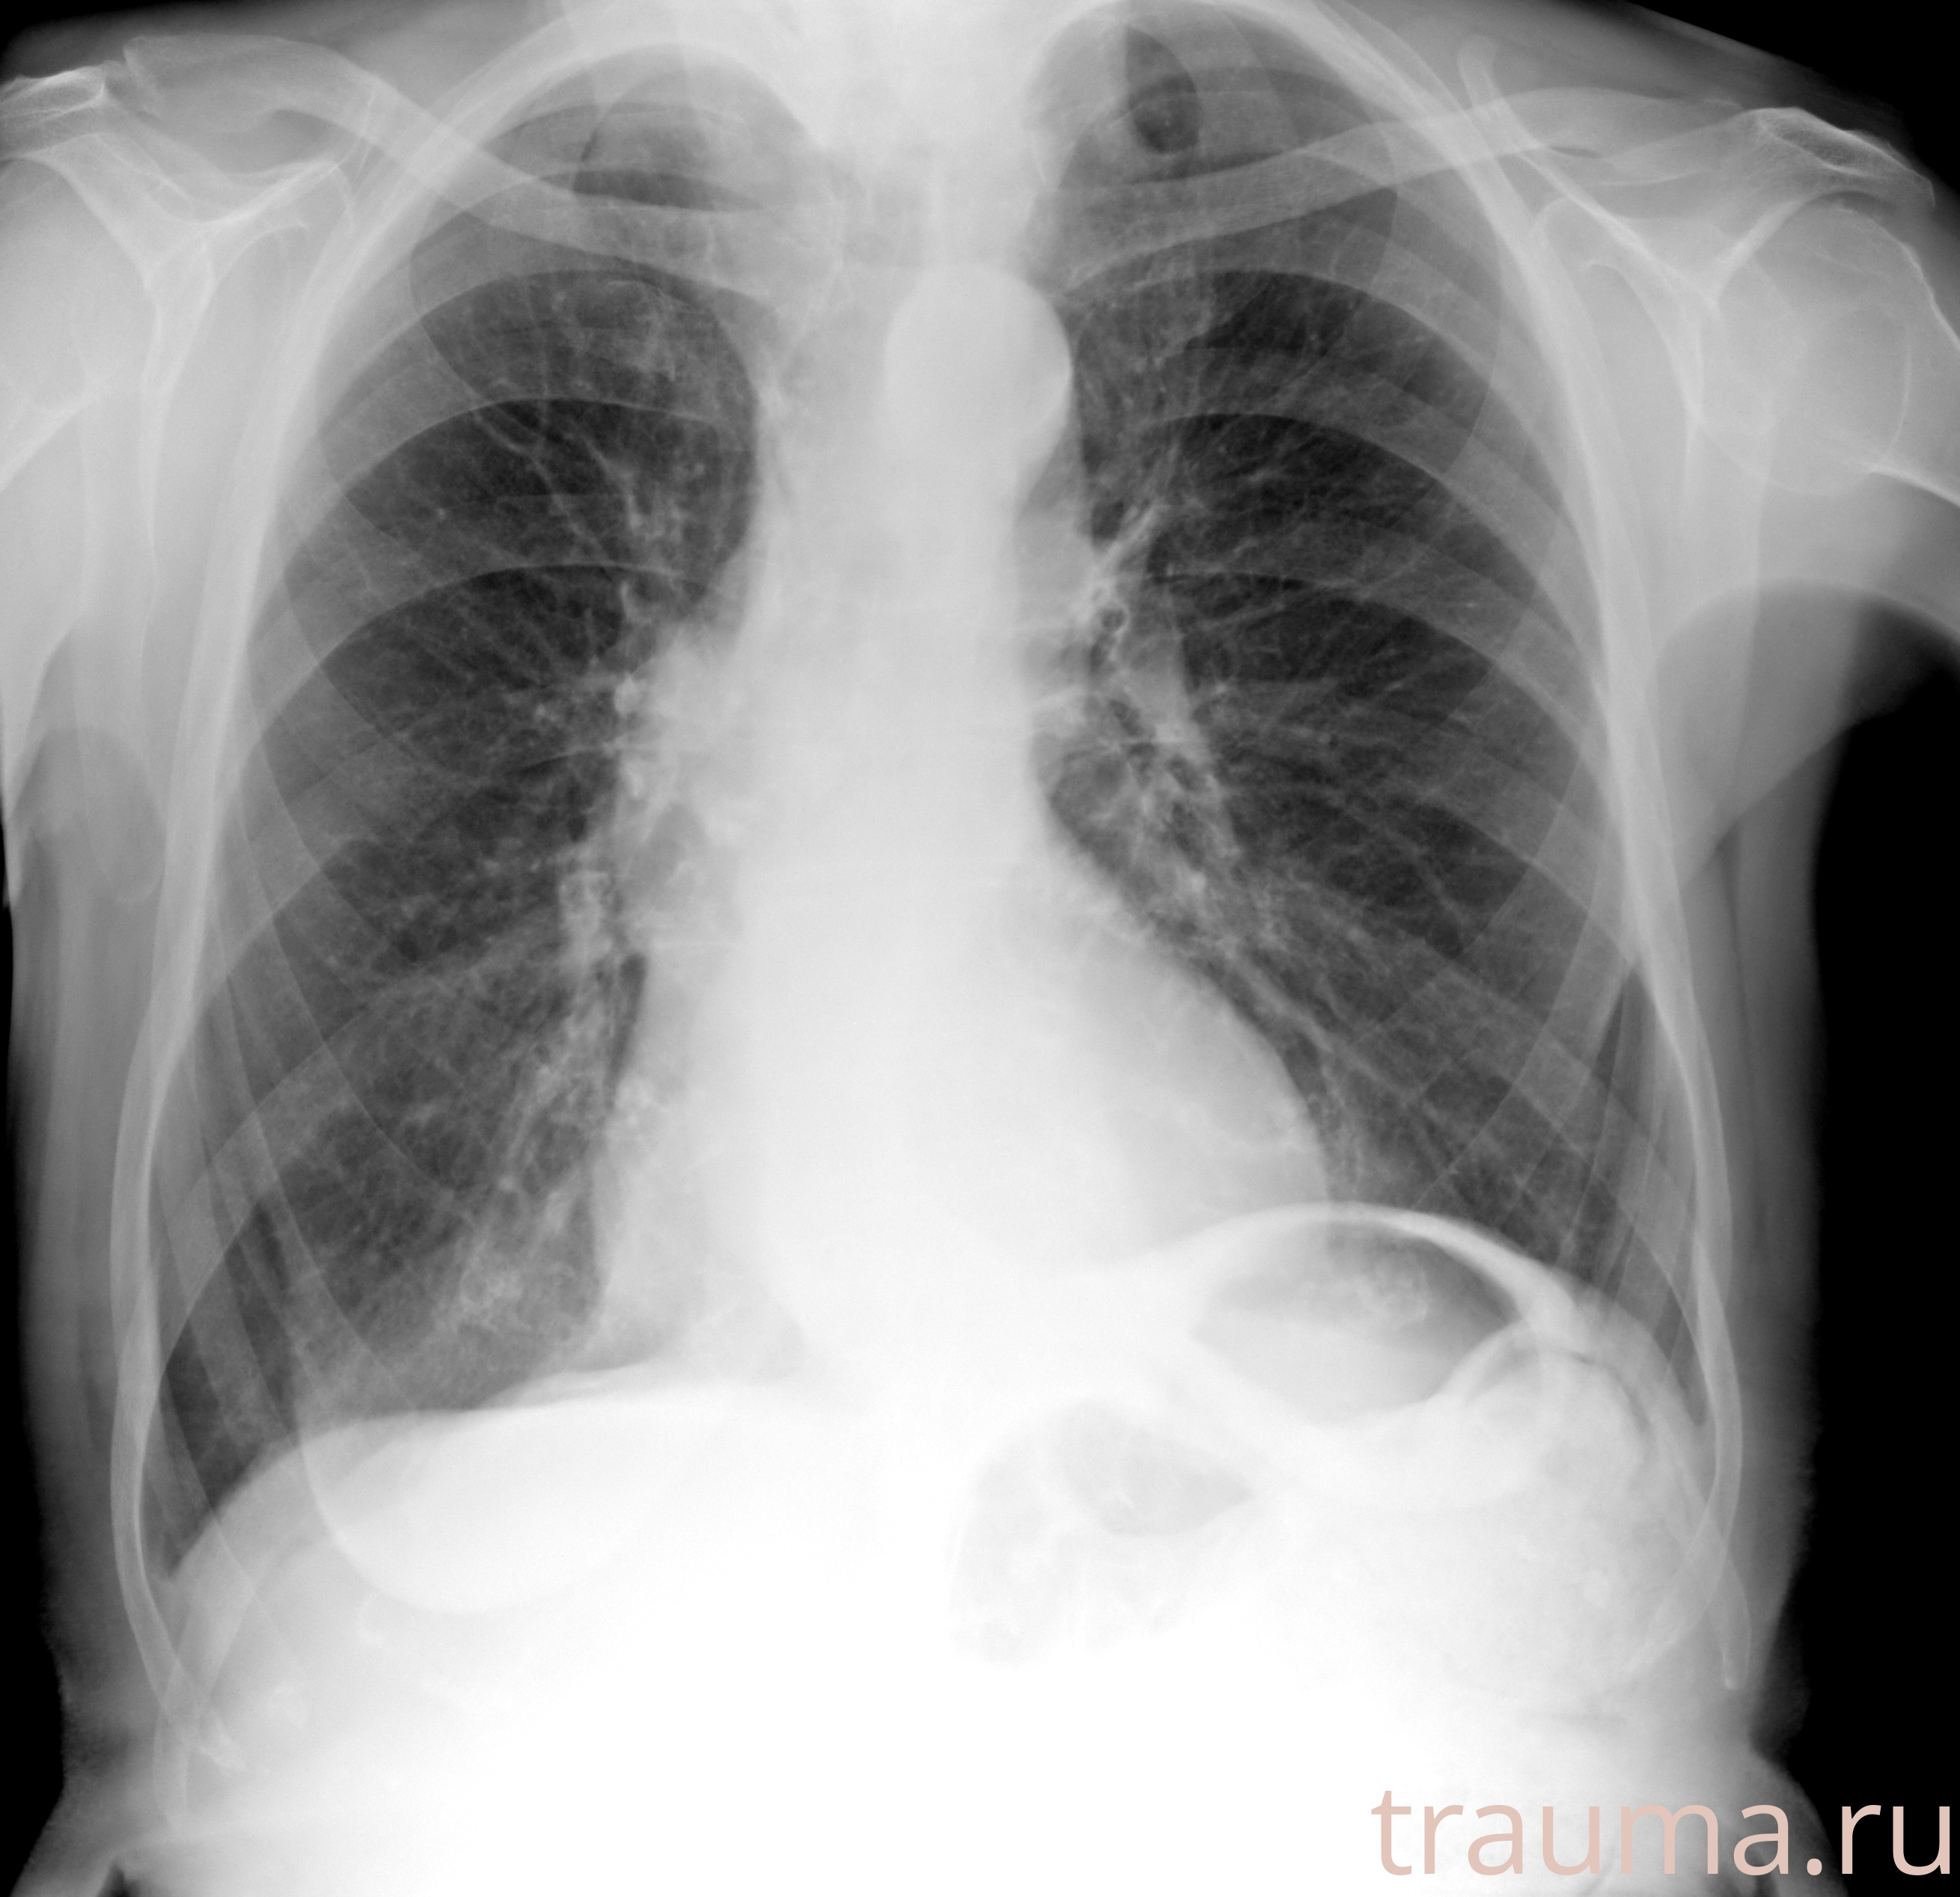

Рентгенограммы

Рентген на дому: по вашему адресу приезжает врач-рентгенолог, травматолог-ортопед с мобильным рентгеновским аппаратом, проводит диагностику травмы или заболевания, делает необходимые рентгенограммы, дает рекомендации по дальнейшему лечению. Получить качественные снимки в домашних условиях возможно благодаря уникальной методике, разработанной МосРентген Центром для института  Склифосовского

при переломе шейки бедра и пневмонии от компании МосРентген Центр - партнера Института имени Склифосовского